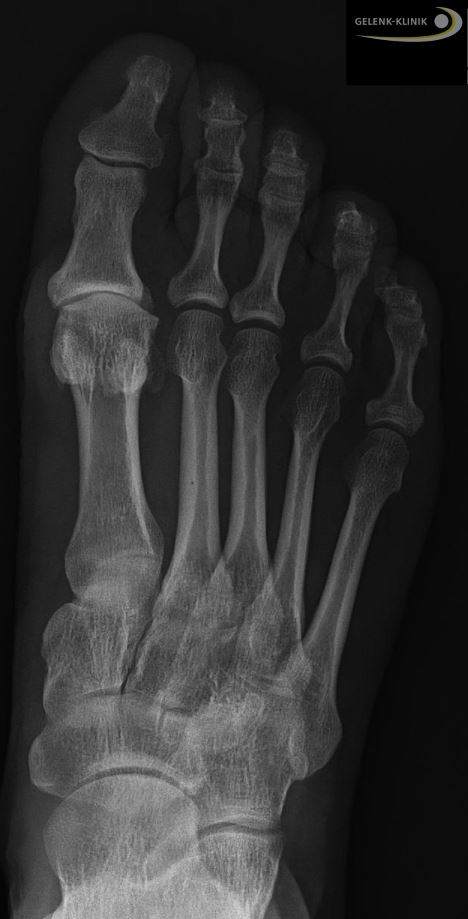

Hallux rigidus im Röntgenbild: Der Gelenkspalt des Großzehengrundgelenks ist aufgrund des fehlenden Knorpels stark verschmälert. © Gelenk-Klinik

Um feststellen zu können, ob eine Hemiprothese für einen Patienten geeignet ist, veranlasst der Arzt eine klinische und radiologische Untersuchung. Wenn symptomatisch Beschwerden bestehen, muss ein Röntgenbild einschätzen, ob eine Arthrose vorliegt. Der Arzt erkennt die Arthrose des Großzehengrundgelenks an einem verschmälerten Gelenkspalt, der auf den fehlenden Knorpel an den Gelenkflächen zurückzuführen ist.

Wenn eine Arthrose als Ursache für die Beschwerden festgestellt werden kann, darf diese ein gewisses Maß nicht überschreiten, damit eine Hemiprothese infrage kommt. Eine sehr fortgeschrittene Arthrose an beiden Gelenkflächen wäre eine Indikation für eine Versteifung des Gelenks. Die Untersuchungen können jedoch auch andere Ursachen als Grund für eine schmerzhafte Bewegungseinschränkung zum Ergebnis haben, sodass sich für Sie eine andere Therapie als optimal herausstellt.